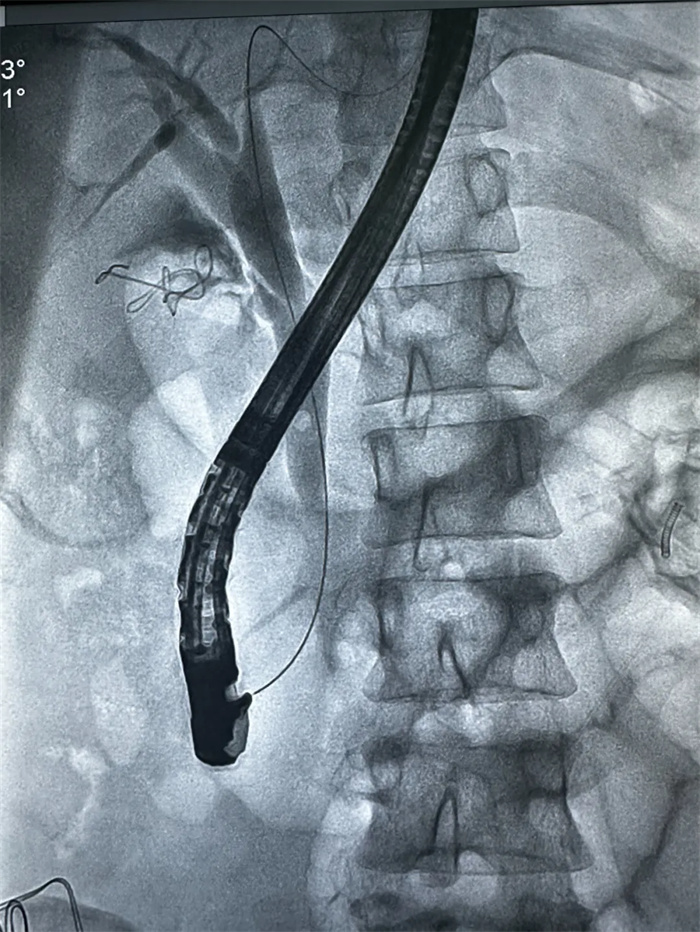

手術(shù)中,榮譽院長楊闖、主治醫(yī)師曹君貴首先進行了LC術(shù),術(shù)中經(jīng)膽囊管插管后,由曹君貴主治醫(yī)師再行ERCP+EST取石+ENBD術(shù),順利解決膽總管結(jié)石。